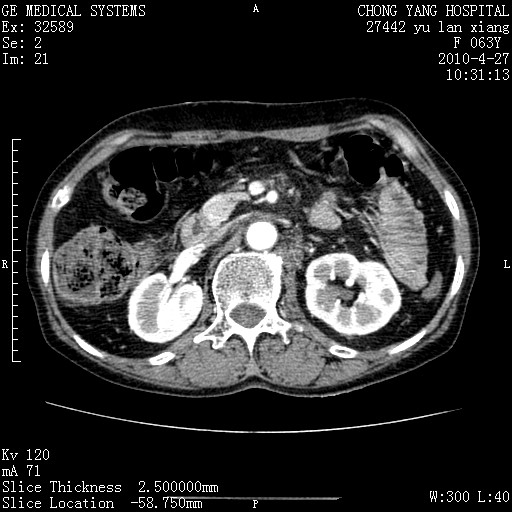

标题: CT26066:F63Y 上腹正中压痛半月,CA199:7400u/ml,MR示胰腺炎伴 [打印本页]

胰腺癌侵犯腹腔动脉干-分支、胃壁、左侧膈肌伴胰周及腹膜后淋巴结转移、胆囊切除术后。

胰腺癌侵犯腹腔动脉干-分支、胃壁、左侧膈肌伴胰周及腹膜后淋巴结转移、胆囊未显影。